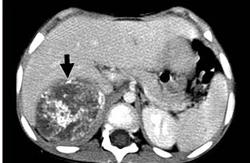

July 5, 2011 – A new treatment option may soon be available for children with neuroblastoma, according to research published in the July issue of The Journal of Nuclear Medicine. The study tested the principle that combined positron emission tomography and X-ray computed tomography (PET/CT) may be used to select children with primary refractory or relapsed high-risk neuroblastoma for treatment with a molecular radiotherapy known as 177Lu-DOTATATE. This therapeutic option was found to be a viable option for children with neuroblastomas. Neuroblastoma is a cancerous tumor that develops from nerve tissue in infants and children. Accounting for six to 10 percent of all childhood cancers, it does not always follow the same pattern, with some patients regressing spontaneously and other progressing, despite aggressive therapy. The long-term survival rate for neuroblastoma is below 40 percent. "We know that peptide receptor radionuclide therapy in adults with somatostatin-positive neuroendocrine tumors has resulted in improved symptoms, prolonged survival and an enhanced quality of life. Since some neuroblastomas express somatostatin receptors, we felt this approach could be beneficial to children as well," said Jamshed B. Bomanji, MBBS, PhD, FRCR, FRCP, one of the authors of the study "177Lu-DOTATATE Molecular Radiotherapy for Childhood Neuroblastoma." In the study, eight children with relapsed or primary refractory neuroblastoma were imaged with a 68Ga-DOTATATE PET/CT scan. If the disease sites showed 68Ga-DOTATATE uptake greater than the liver, the child was considered eligible for the molecular radiotherapy. Therapy with 177Lu-DOTATATE was determined to be suitable for six of the children and was administered appropriately. After completing treatment with 177Lu-DOTATATE, five children had stable disease by the response evaluation criteria in solid tumors. The treatment was feasible, practical and well-tolerated in the small group of patients with high-risk neuroblastoma. As a result, the researchers plan to evaluate 177Lu-DOTATATE formally in a phase I-II clinical trial to evaluate toxicity and response. "Molecular imaging has contributed a new diagnostic technique to map the full extent of disease. This mode of treatment has great potential for children whose treatment options are limited, as neuroblastoma often becomes resistant to chemotherapy and success is limited by poor bone marrow reserve," said Bomanji. For more information: www.snm.org